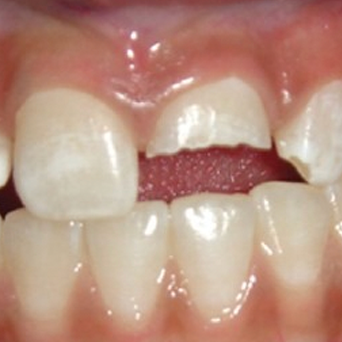

치아파절

외상으로 치아가 깨지거나 부러진 경우

주요 증상

- 신경 노출

- 날카로운 통증

- 시림 증상